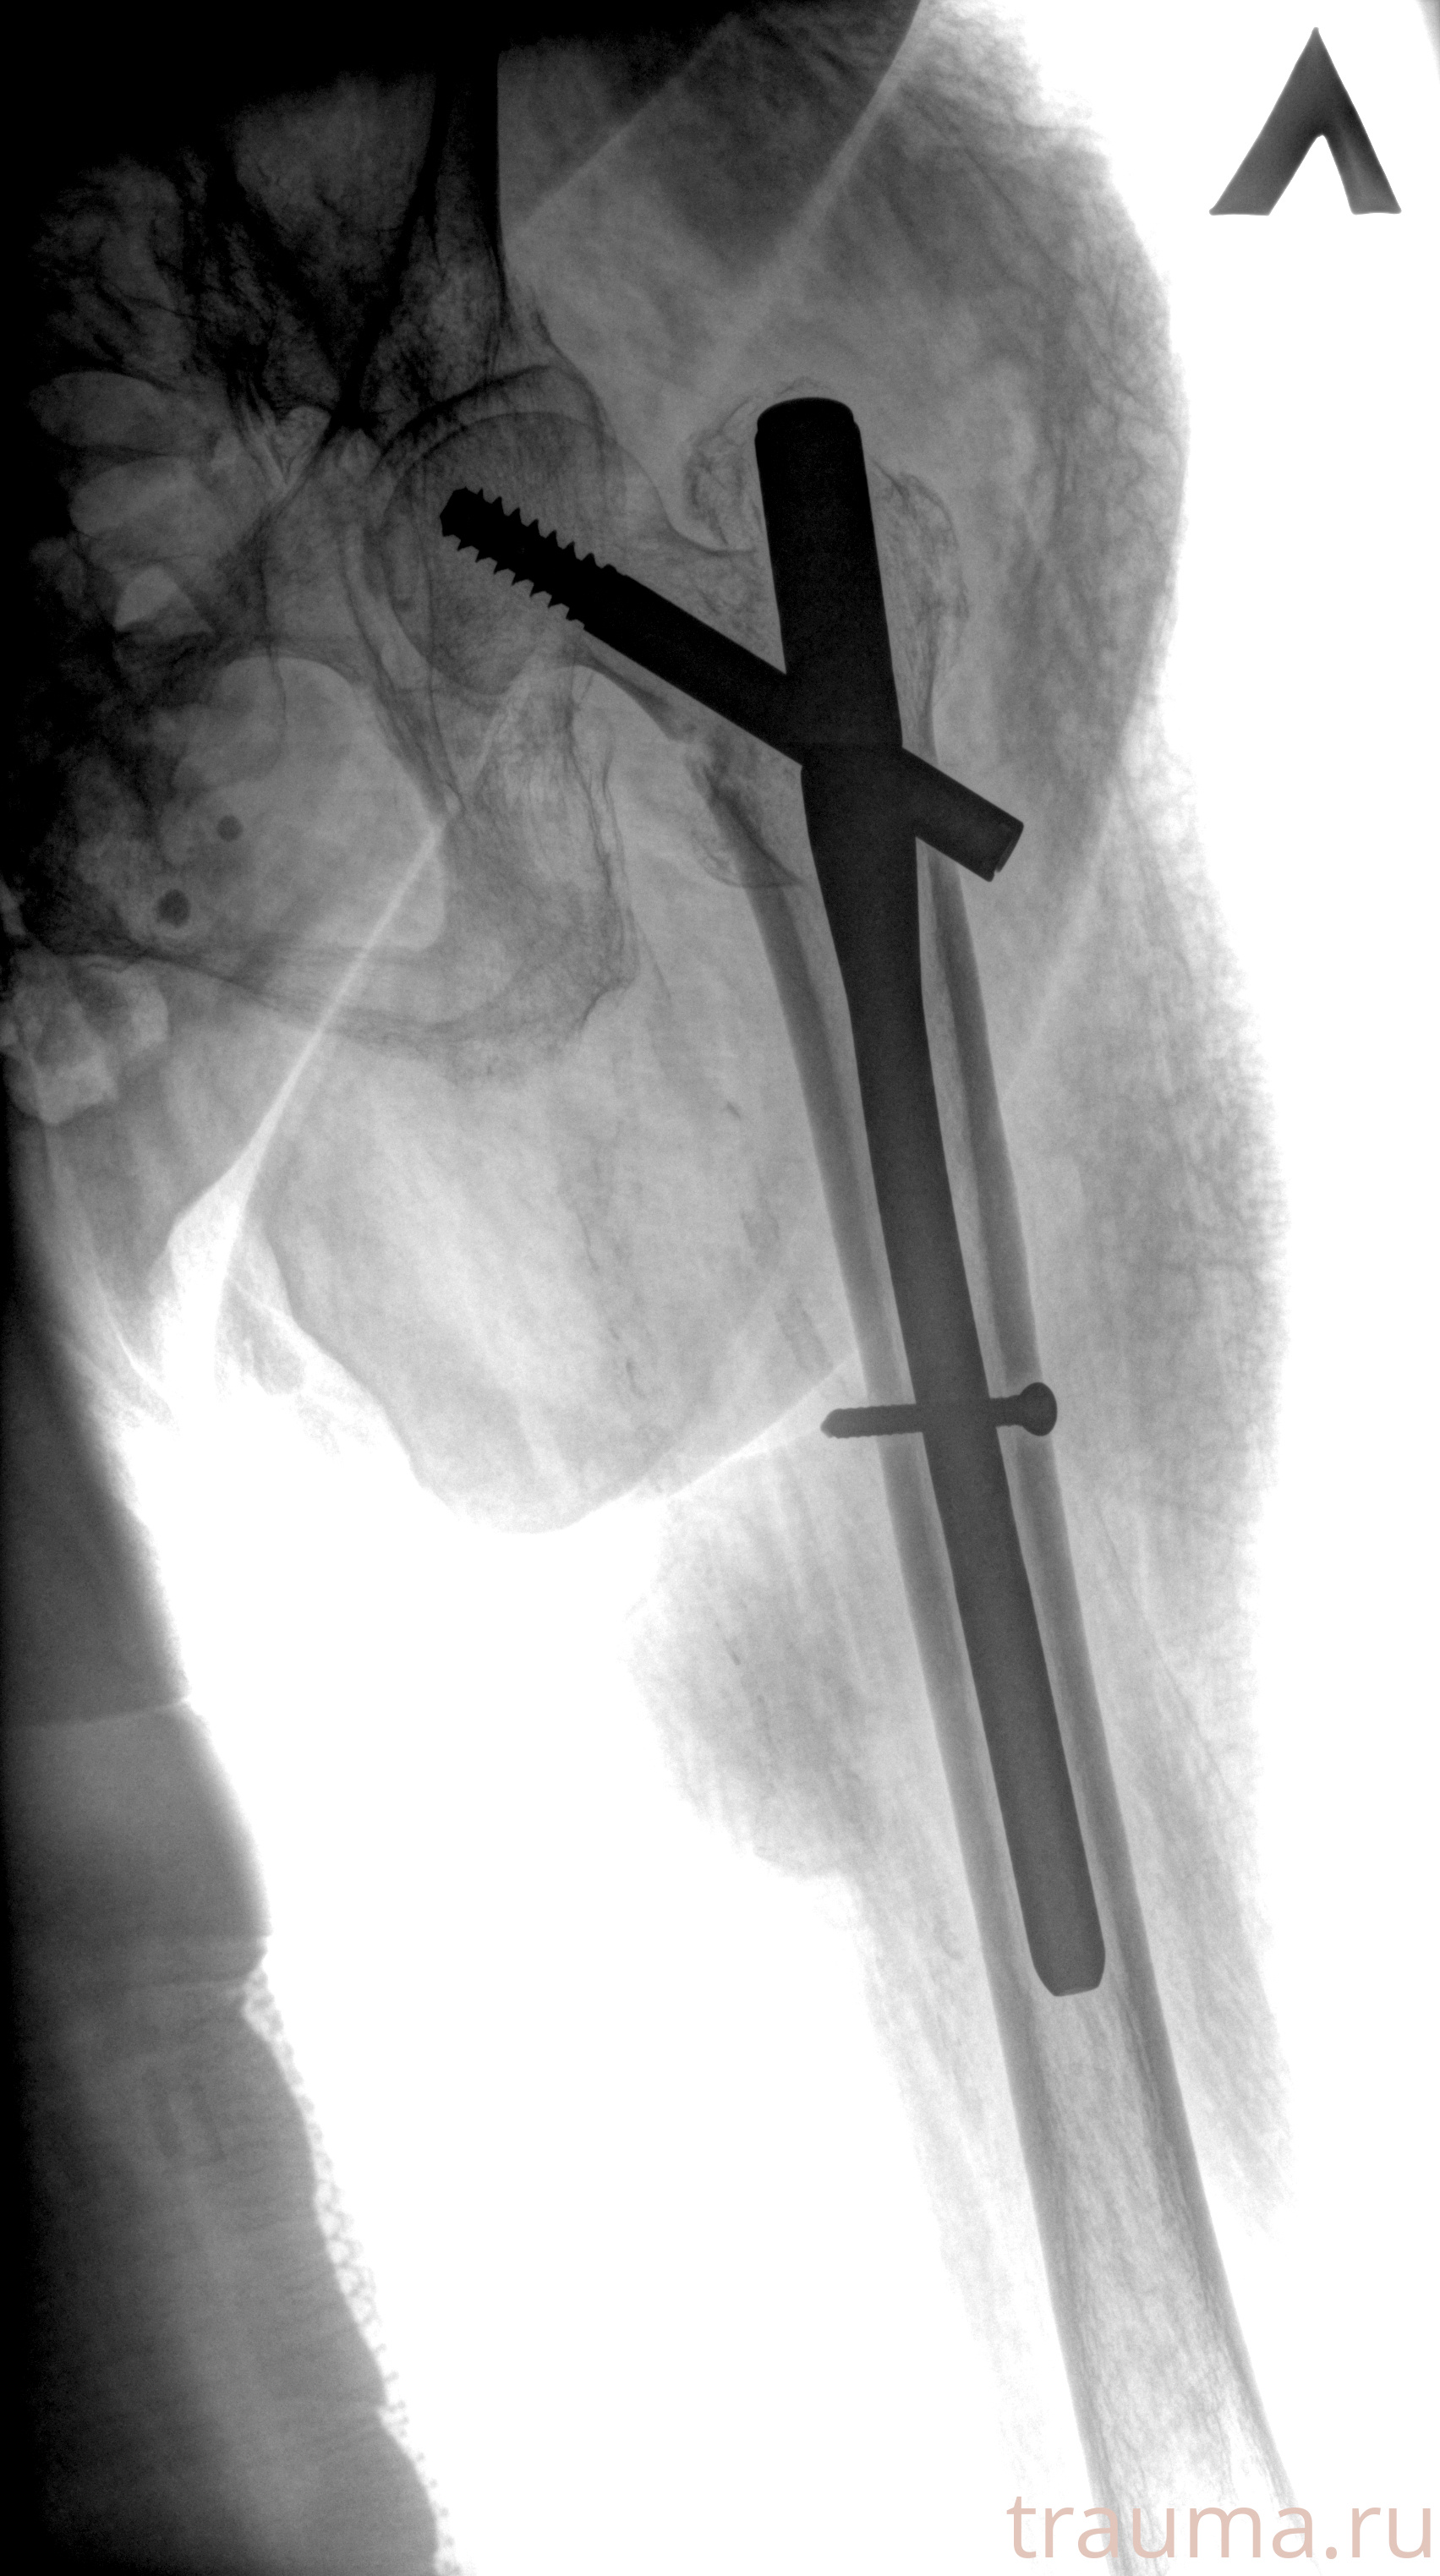

Рентгенограммы

Рентген на дому: по вашему адресу приезжает врач-рентгенолог, травматолог-ортопед с мобильным рентгеновским аппаратом, проводит диагностику травмы или заболевания, делает необходимые рентгенограммы, дает рекомендации по дальнейшему лечению. Получить качественные снимки в домашних условиях возможно благодаря уникальной методике, разработанной МосРентген Центром для института  Склифосовского